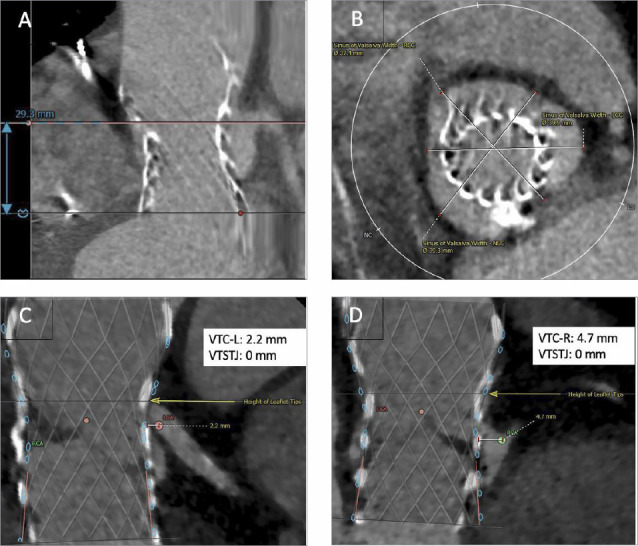

How to Assess the Feasibility of a Second Transcatheter Aortic Valve Replacement When the First Valve Fails.

当第一次主动脉瓣置换术失败时,如何评估第二次经导管主动脉瓣置换术的可行性?